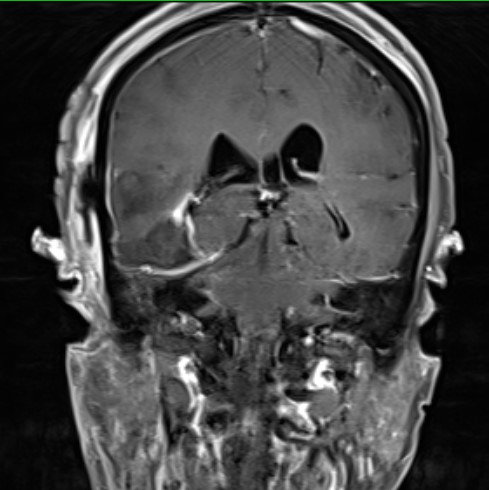

冠状位

术后复查肿瘤近全切除